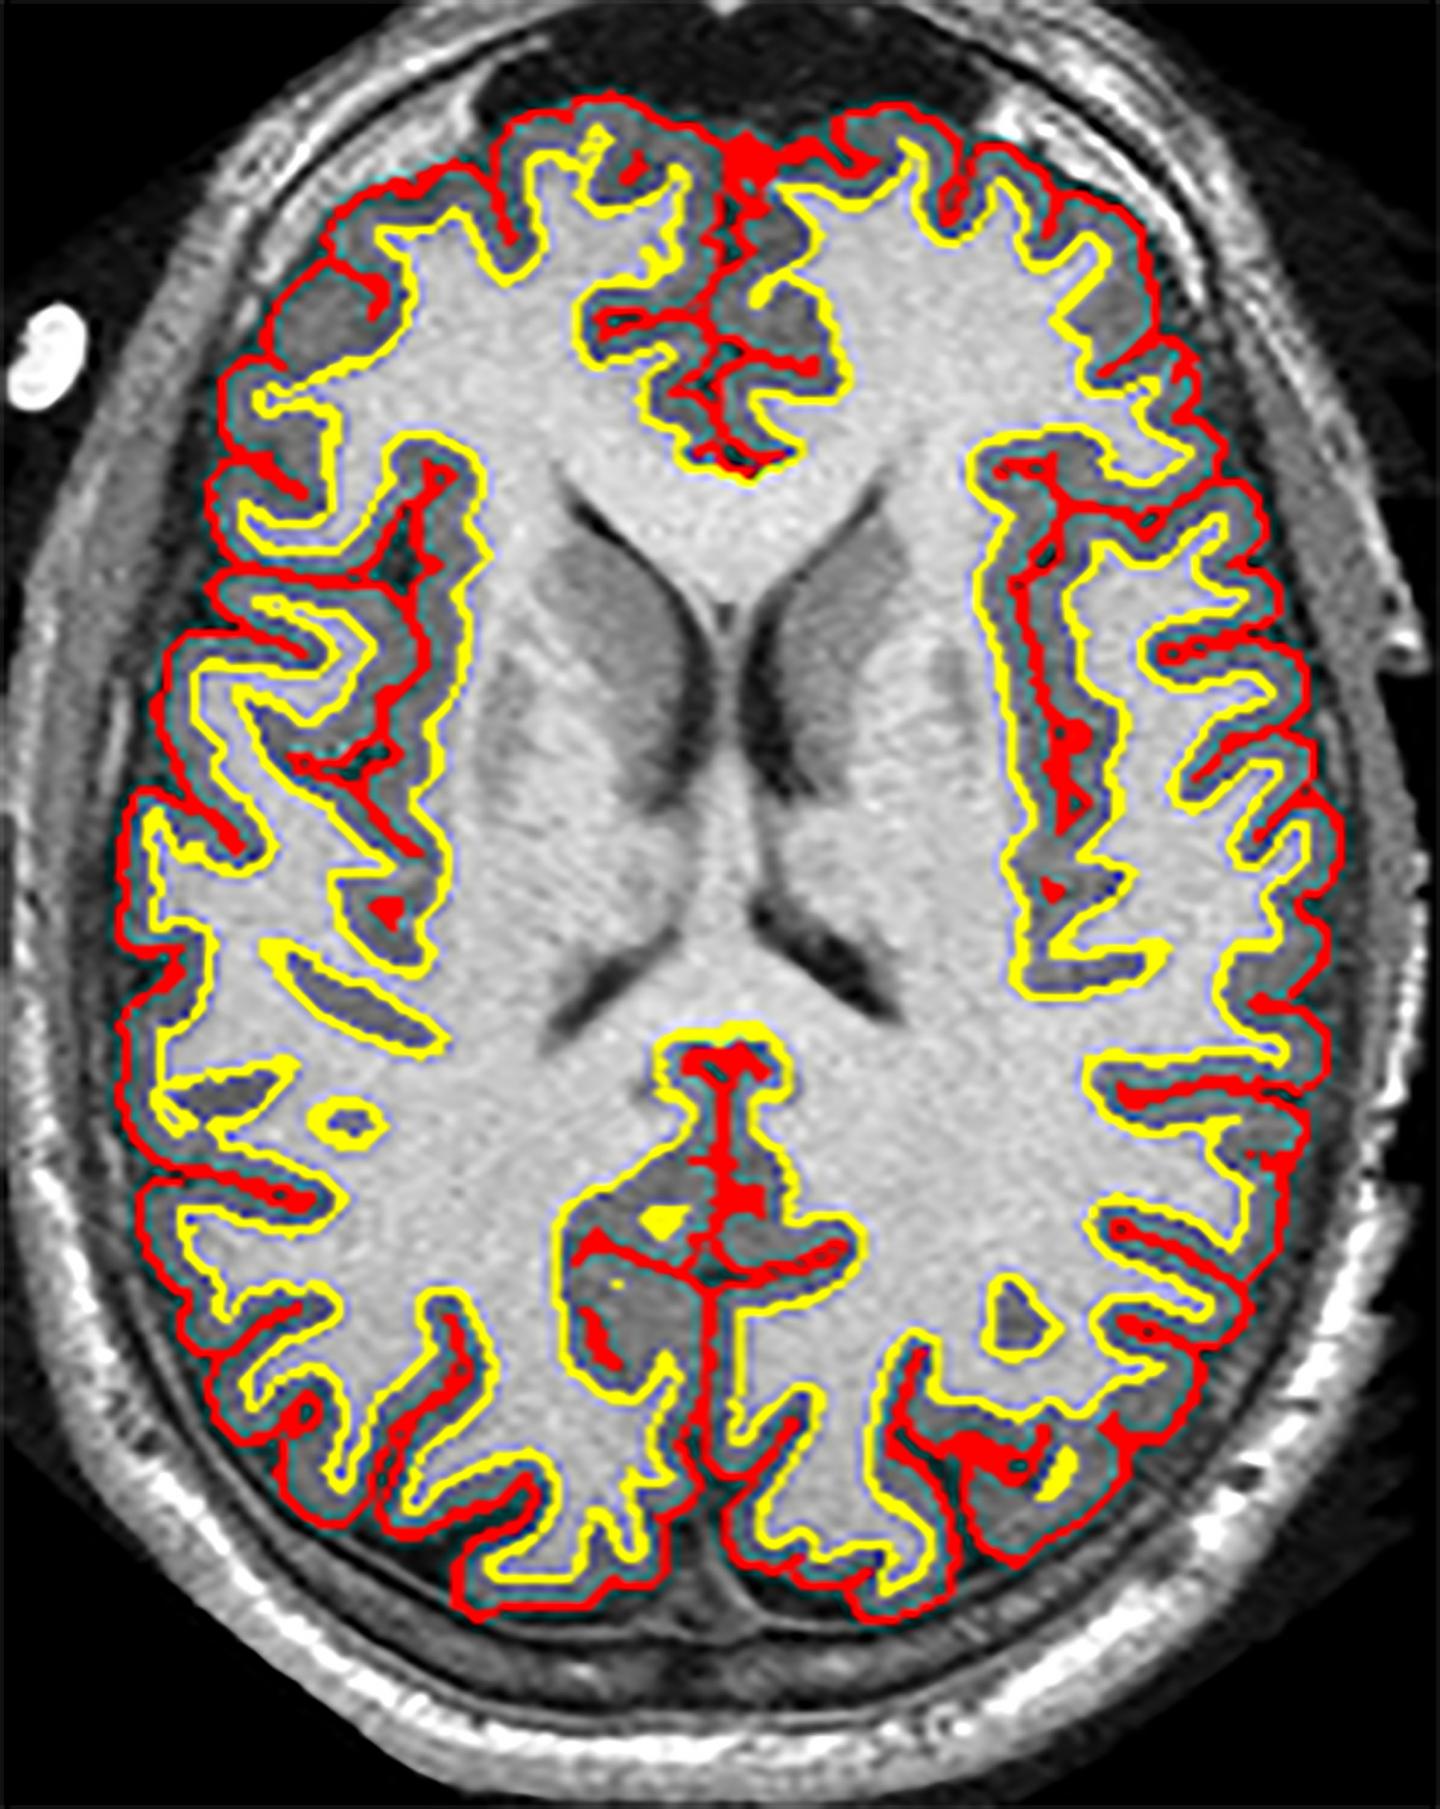

image: An NIH-funded clinical trial suggested that the anti-inflammatory drug ibudilast may slow brain shrinkage caused by progressive MS.

Courtesy of Robert J. Fox, M.D., Cleveland Clinic, OH.

Robert J. Fox, M.D., a neurologist at Cleveland Clinic in Ohio, led a team of researchers across 28 clinical sites in a brain imaging study to investigate whether ibudilast was better than placebo in reducing the progression of brain atrophy, or shrinkage, in patients with progressive multiple sclerosis.

In the study, 255 patients were randomized to take up to 10 capsules of ibudilast or placebo per day for 96 weeks. Every six months, the participants underwent MRI brain scans. Dr. Fox's team applied a variety of analysis techniques on the MRI images to assess differences in brain changes between the two groups.